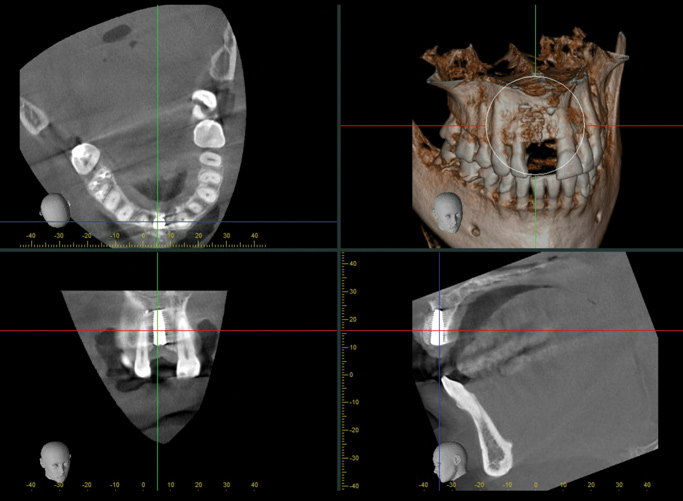

When the patient returned 4 months after the initial procedure for reevaluation, she underwent supportive periodontal therapy and was provided with detailed oral hygiene instructions (Figure 13). An intraoral scan and a postoperative CBCT scan were taken to evaluate both the horizontal and vertical hard- and soft-tissue gain. Next, implant planning software was used to merge the STL and DICOM data, which facilitated the creation of a digital wax-up (Figure 14).

The digital wax up allowed the implant position to be planned based on the ideal prosthetic position of the final restoration (Figure 14). The planned implant position adhered to the aforementioned guidelines for ideal implant placement regarding the buccal, interproximal, and apical bone, and its platform would be located 4-mm apical to the planned restorative margin. In the coronal plane, the implant was centered with the gingival zenith in a position that was located approximately 1-mm distal to the midline of the edentulous space. Following implant planning, a tooth-supported surgical guide was designed and then 3D-printed to facilitate fully guided surgical implant placement.

(7.) Pretreatment CBCT scan.

Figure 7

(14.) Three-dimensional implant treatment planning.

Figure 14

(22.) Immediate postoperative CBCT scan.

Figure 22